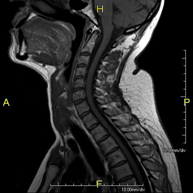

- RM Columna Cervical

Prueba diagnóstica no invasiva que consiste en la obtención de imágenes de alta definición anatómica de la columna cervical mediante el empleo de un campo electromagnético y ondas de radio (con un emisor y un receptor). No utiliza radiación ionizante. Indicaciones: traumatismo, degeneración de la columna, hernias. - RM Columna Dorsal